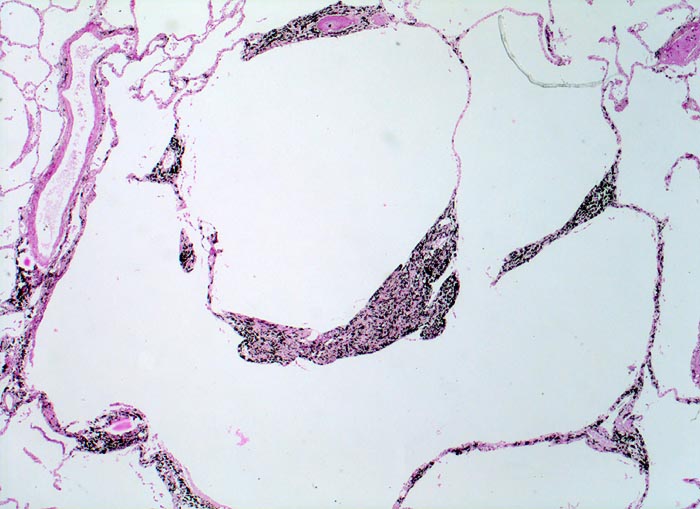

zentroazinäres Lungenemphysem

Stark erweitertes Azinuszentrum erkennbar am schwarzen Anthrakosepigment. Die Alveolarsepten erscheinen fragmentiert: Bruchstücke von Alveolarsepten und Gefässen scheinen ohne Verbindung mit dem übrigen Gewebe im Zentrum der emphysematischen Räume zu liegen

Makroskopisch erscheinen die destruierten Azinuszentren als schwarz umrandete unterschiedlich grosse Löcher.

Histologie

25